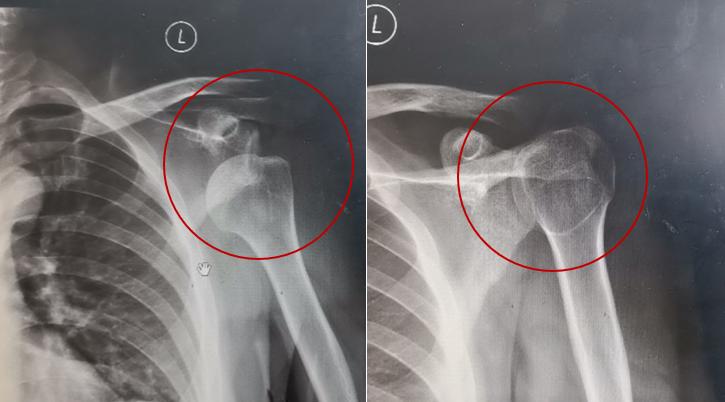

27岁的蔡先生当时满头大汗、表情扭曲,骂骂咧咧外加呻吟着进了诊室。 简单问了一下情况得知,蔡先生今天刚发工资,就去了一家心仪已久的“高档”泰式SPA会馆,做了个泰式按摩,结果把自己“按”进了医院。

简单问了一下情况得知,蔡先生今天刚发工资,就去了一家心仪已久的“高档”泰式SPA会馆,做了个泰式按摩,结果把自己“按”进了医院。据他讲述,按摩师从脚开始,依次往上按压全身的各个关节。按到肩关节时,先是做了一些旋转、撑起的动作,接下来一提拉时,“咯噔”一声,悲剧发生了。蔡先生的左肩当时就不能动了……

(不当按摩动作模拟,请勿模仿) (不当按摩动作模拟,请勿模仿)伤的虽然是肩膀,但从急诊室到X线室的路上,每一步他都走得很艰难……

(不当按摩动作模拟,请勿模仿)伤的虽然是肩膀,但从急诊室到X线室的路上,每一步他都走得很艰难…… (X线片显示,蔡先生的左肩关节脱位。作者供图)复位治疗后,终于没那么疼了。但接下来,小蔡还要经历6个星期的肩关节固定、制动休息,也就是俗称的“打石膏”,生活工作都很不方便,真是无妄之灾啊。

(X线片显示,蔡先生的左肩关节脱位。作者供图)复位治疗后,终于没那么疼了。但接下来,小蔡还要经历6个星期的肩关节固定、制动休息,也就是俗称的“打石膏”,生活工作都很不方便,真是无妄之灾啊。 03 推拿本为放松,没想到推断了腰